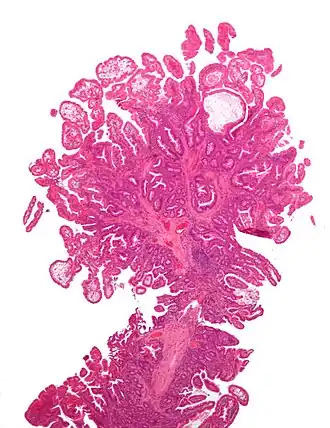

een peutz-jegherstype poliep uit de darm op kleine vergroting